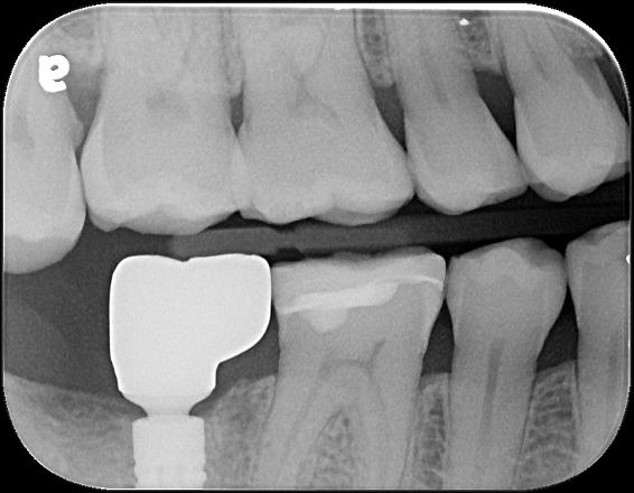

治療前,二次蛀牙,咬頭受損

蛀牙未到牙髓